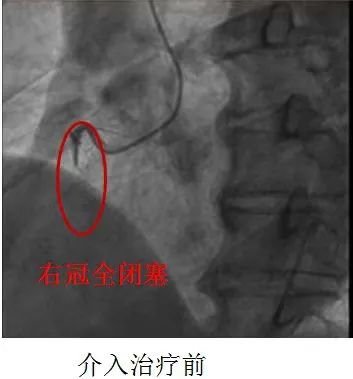

该患者男性71岁,因“胸痛、胸闷2小时”就诊社区医院,社区医院行心电图检查提示:急性下壁心肌梗死,社区医院建议转院治疗,于10点05分家属拨打急救电话进行转院。10分钟后急救车到达社区医院,120医生将心电图传至医院胸痛中心微信群,通过心内科值班医生进行会诊后确定急性心肌梗死应该进行冠脉介入治疗,120医生随即与患者及家属沟通,告知病情及治疗方案,家属同意绕行急诊直接进入导管室介入治疗。

11点14分患者到达医院直接送至导管室。

20分钟后患者导丝通过病变血管堵塞的血流恢复。